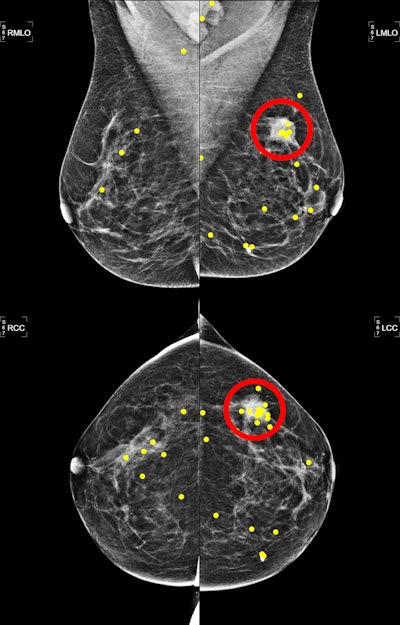

Mammograms depict a 54-year-old woman with an invasive ductal carcinoma in the lateral upper quadrant of the left breast. The yellow dots represent eye fixations, and the red circle represents the lesion region. Image courtesy of the RSNA.

The analysis included screening mammograms performed between 2016 and 2019 for 150 women with a median age of 55 years. Of the mammograms, 75 had breast cancer while the remaining 75 did not. The screening exams, each consisting of four mammograms, were interpreted by 13 radiologists in three distinct orders: randomly, by increasing volumetric breast density, and based on a self-supervised learning encoding. The researchers also employed an eye tracker to record eye movements by the radiologists.